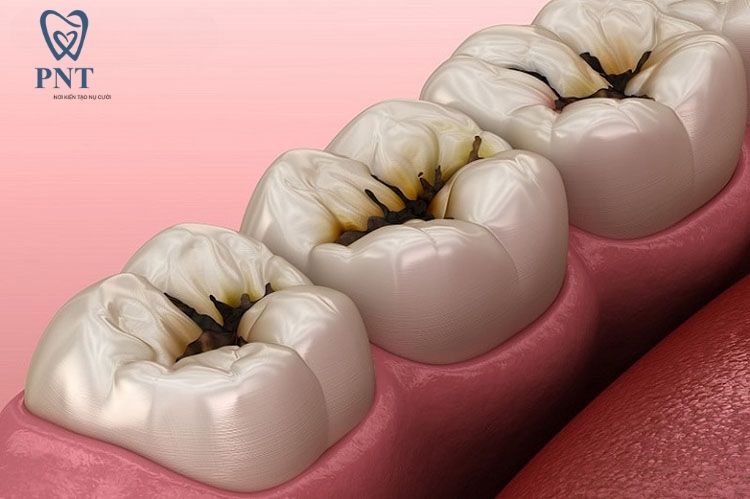

Đau răng sâu là gì? Vì sao sâu răng lại gây đau nhức?

Đau răng sâu là gì?

Đau răng sâu là tình trạng đau nhức xảy ra khi răng bị vi khuẩn tấn công, làm phá hủy men răng và ngà răng. Khi tổn thương lan sâu vào bên trong, đặc biệt là đến tủy răng – nơi chứa các dây thần kinh, cảm giác đau sẽ trở nên rõ rệt và dữ dội hơn.

1. Vi khuẩn xâm nhập vào tủy răng

Khi sâu răng không được điều trị sớm, vi khuẩn sẽ phá vỡ lớp bảo vệ tự nhiên của răng và tiến sâu vào buồng tủy. Tại đây, các dây thần kinh bị kích thích, gây ra cơn đau nhức dữ dội, có thể đau liên tục hoặc đau từng cơn.

2. Gia tăng áp lực bên trong răng

Quá trình viêm nhiễm do vi khuẩn gây ra làm tăng áp lực trong răng, đặc biệt là khi có ổ viêm hoặc mủ. Đây là nguyên nhân khiến nhiều người bị đau răng sâu nặng hơn vào ban đêm.

3. Răng trở nên nhạy cảm

Khi lớp men răng bị tổn thương, răng sẽ nhạy cảm hơn với nhiệt độ và thức ăn. Chỉ cần ăn đồ nóng, lạnh, ngọt hoặc chua cũng có thể gây ê buốt và đau nhức.

4. Hình thành áp xe răng

Sâu răng nặng có thể gây viêm nhiễm lan rộng, hình thành túi mủ (áp xe) ở chân răng, dẫn đến sưng má, sốt, đau dữ dội và nguy cơ biến chứng nguy hiểm.